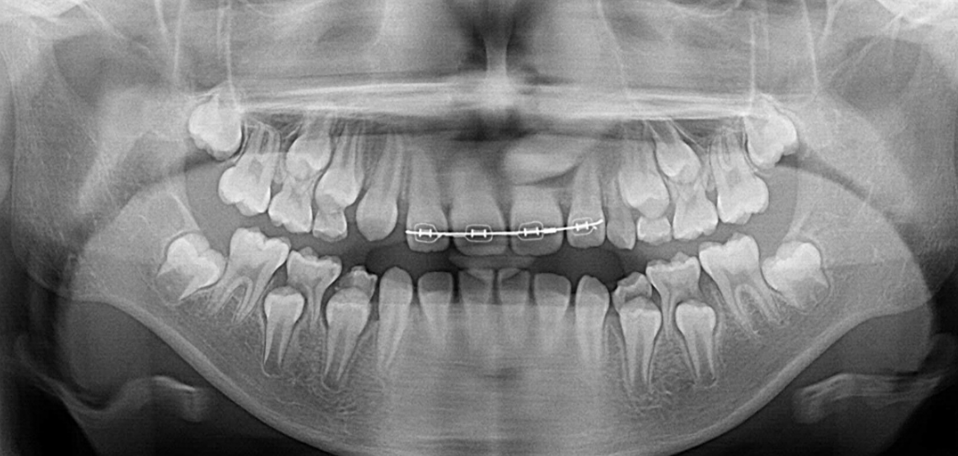

ヒルサイドビュー矯正歯科の特徴は、成長期のお子様の矯正治療において、アゴの成長のタイミングを見極めた治療を実践している点です。単に歯並びを整えるだけでなく、顔立ちの将来的な変化も考慮に入れた包括的な治療を行います。また、矯正治療において重要な役割を果たす顎関節の安定性を重視し、治療開始前に十分な検査と調整を行うことで、より確実な治療結果を目指しています。

MRI検査を用いて顎関節の状態を詳細に分析し、下アゴの成長時期を的確に判断します。この診断により、矯正治療の最適なスタート時期を決定し、患者様の成長に合わせた治療計画を立案いたします。特に成長期のお子様の場合、アゴの成長を促す環境を整えることを重視し、不必要な装置の使用を避け、成長を阻害しない治療を心がけています。

矯正装置には、世界標準のエッジワイズ装置(Straight Wire Appliance)を採用し、精密な歯の移動を実現します。治療中は定期的にTMJの状態を確認し、必要に応じて調整を行うことで、安定した治療結果を目指します。治療終了後も、ポジショナーとリテーナーを併用した管理を行い、治療結果の維持に努めています。ヒルサイドビュー矯正歯科の矯正治療は、歯並びの改善だけでなく、顔立ちの調和と機能的な咬み合わせの獲得を目標としています。